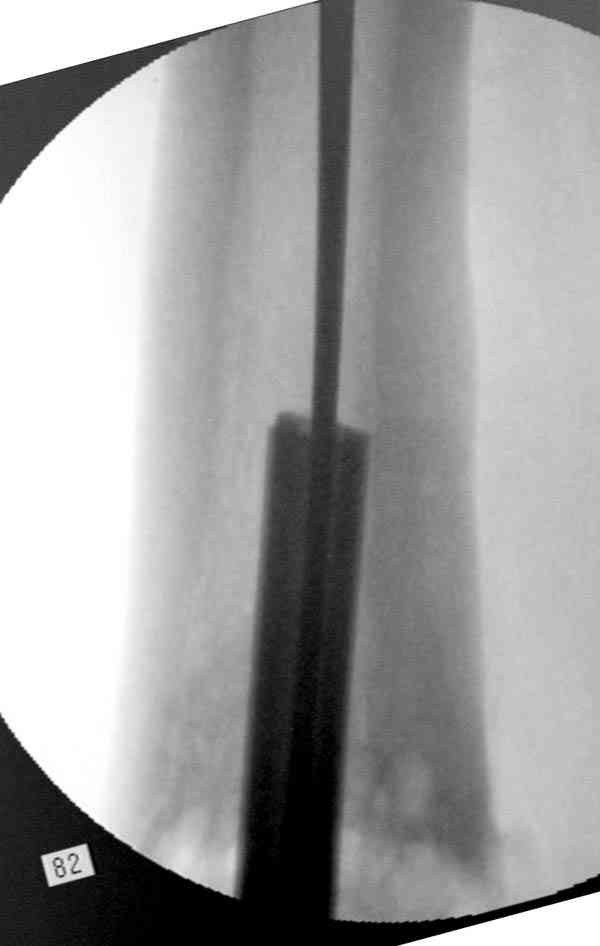

Уважаемые коллеги! У пациента 50-ти лет ложный сустав голени, перелом интрамедуллярного штифта. Перелому около 2 лет, ходить с полной нагрузкой начал через 3 мес. после операции. Боли при ходьбе почувствовал около 2 мес. назад. На данный момент ходит с полной нагрузкой без посторонней опоры. Среди коллег развернулась дискуссия по поводу способа оперативного лечения: -удаление штифта с перештифтовыванием блокированным штифтом с рассверливанием и остеотомией м\б кости -стабилизация зоны ложного сустава по медиальной поверхности LCP-пластиной с декортикацией или без -удаление штифта или без и синтез в АВФ с декотрикацией или без и остеотомией м\б кости

Периферический отломок стержня - наверно, надо воспользоваться отверстием, над ним сделать трепанацию и через него вверх провести длинную спицу, сделав на ее нижнем конце крючок. Лучше уже перед этим рассверлить центральный отломок.

Приспособление для удаления сломанных штифтов и наличие ЭОП облегчит задачу. При отсутствии крючка тогда можно применить обычный длинный ball pointed guide wire от интрамедулярного набора. Проволока, пропущенная за пределы гвоздя и зажатая другая вытащат сломанный конец штифта без проблем.